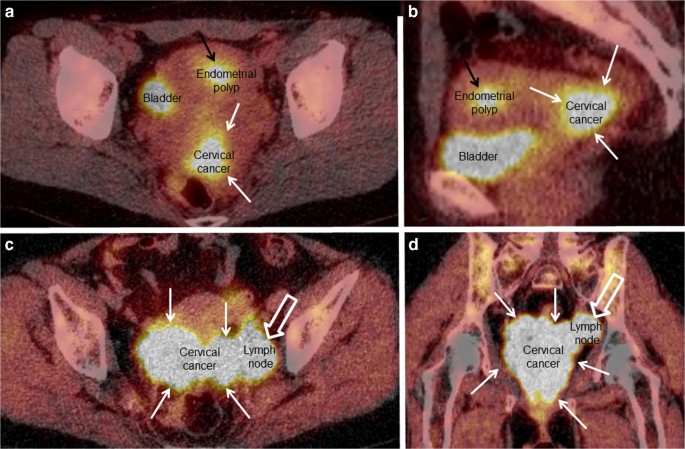

Imaging And Cancer Of The Cervix In Low And Middle Income Countries Sciencedirect